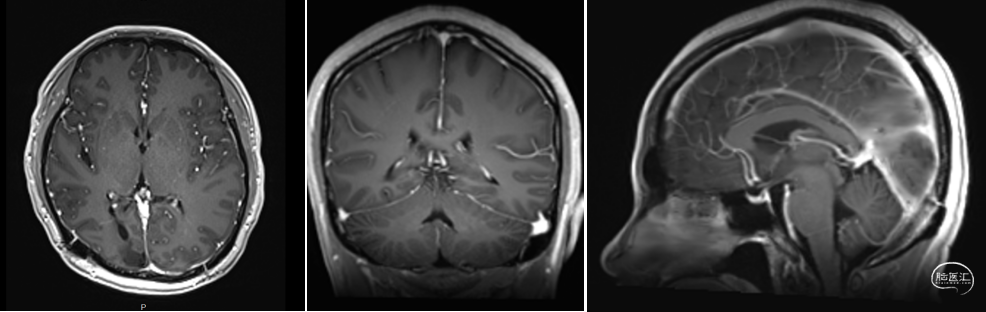

术前MRI

手术风险评估:肿瘤位于脑中央深部,毗邻重要功能结构,与大脑内静脉、大脑大静脉、脉络膜后内侧动脉、中脑顶盖关系密切,肿瘤血管丰富,可能来源于脉络膜动脉及其分支。

手术入路选择:采用枕部经右侧皮层造瘘+左侧纵裂/大脑镰入路,增加的对侧视野的暴露,同时右侧皮层造瘘,避免过多牵拉双侧枕叶、避免损伤重要血管结构及重要的神经纤维束。

本例患者影像学上表现为累及胼胝体压部的典型的蝴蝶状胶质瘤,病变累及双侧半球,非对称分布。手术均用右侧顶枕叶造瘘+左侧纵裂入路,术中先后探查和分块切除大脑镰后部两侧的病变。大脑镰后部毗邻大脑深部静脉系统,需要尽可能避免损伤Galen静脉或下矢状窦等重要结构,左侧纵裂入路可能有利于实现更好的功能保护。位于胼胝体不同部位的蝴蝶状肿瘤,由于解剖基础和功能保护的需求,采取不同的入路,从而在尽可能保护脑功能的前提下安全切除病变。